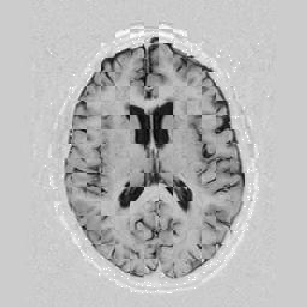

Another larger group of experiments enabled me to study the effects of multi-scale NRR. The results are shown in the form of chequerboard images in Figure [*]. In terms of resolution levels, higher numbers mean that the images are coarser.

Figure: Multi-scale NRR (increasing resolution). From left to right, top then bottom:before NRR; after 5 iterations of NRR at level 2 (higher is coarser); after another 5 iterations of NRR at level 1.